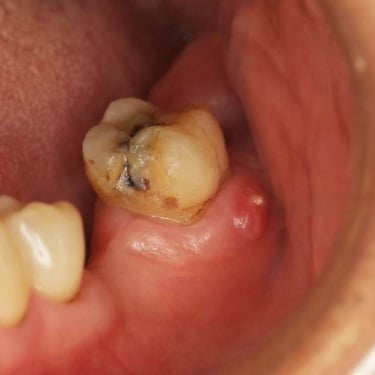

Pulpitis Crónica Hiperplásica

La pulpitis crónica hiperplásica es una inflamación de la pulpa con crecimiento excesivo de tejido pulpar a través de una caries abierta.

Los pacientes notan un tejido rojo que sobresale de la cavidad dental.

El tratamiento incluye la eliminación del tejido afectado y un tratamiento de conducto. Es crucial tratar la caries para evitar infecciones adicionales.